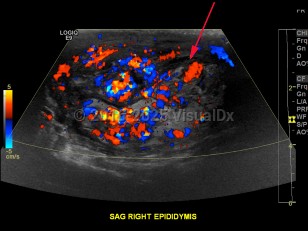

Imaging Studies image of Epididymo-orchitis - imageId=8358339. Click to open in gallery.  caption: '<span>Color Doppler ultrasound image demonstrating increased flow within the epididymis, consistent with epididymitis.</span>'

Color Doppler ultrasound image demonstrating increased flow within the epididymis, consistent with epididymitis.